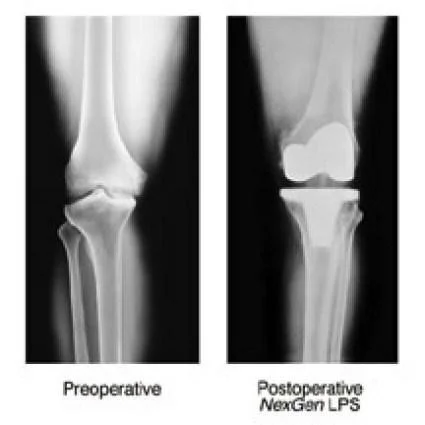

Corrective Osteotomy

- Realign axis & Redistribute weight bearing

- Indication:

- young patients with mild to moderate OA

- Thin & active with mobile joint

- Knee

- Valgus producing proximal tibial osteotomy

Arthroplasty:

- Joint replacement

- Partial

- Total

Total Joint Arthroplasty:

-

Replacing the native joint with prosthesis

Indicated:

- Old patient with deformed, stiff & painful joint.